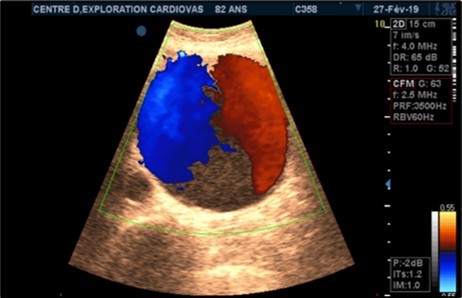

Aneurysms were thrombosed in 24 patients (75%). (Figure 3) and (Figure 4) Arterial occlusion was found in 11 patients (73.33%) and significant stenosis in 4 patients (36.36%). (Table 7).

Figure 3.Large fusiform subrenal abdominal aortic aneurysm of 9.28cm thrombosed at 4/5 in an 82-year-old woman (CEC ‘Saint-Esprit’ from AMP-MCV).

Figure 4.Large fusiform subrenal abdominal aortic aneurysm of 9.28cm thrombosed at 4/5 in an 82-year-old woman (CEC ‘Saint-Esprit’ from AMP-MCV).

The aneurysms had extensions to other arteries in 21 patients (65.63%) distributed as follows: superior mesenteric artery (11.76%) (Figure 3) and (Figure 4), celiac trunk (14.23%), iliac arteries (57.14%) femoral arteries (19.05%). (Figure 5) and (Figure 6)